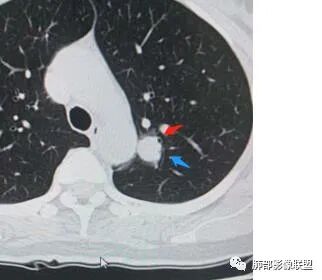

4、血管连通 移动:3型?4型?

两条都进入,相互交通-4

血管进入增粗,胸膜牵拉

金豆

有月牙 两条都进入,相互交通-4 胸膜牵拉

有一条血管进入

而且增粗了

密度确实周围稍低,中央偏高一些

边界清

支持原位?微浸润